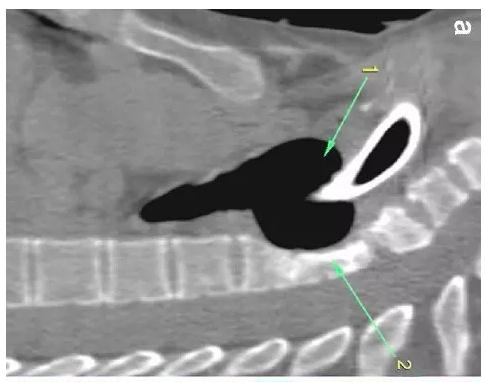

胸部CT显示气切套管气囊周围气管扩张,胸1-4椎体前部受到侵蚀(下图a-c)。

下图箭头1为气切套管气囊紧贴T1-4椎体水平,造成椎体前部受到侵蚀(箭头2):

作者推测患者骨质吸收、骨髓炎与气切套管气囊过度膨胀有关,为气囊过度膨胀造成椎体血流灌注降低所致。在我院住院期间,我们也发现高气囊压力才能防止漏气。经食道内镜检查未发现气管食管瘘。